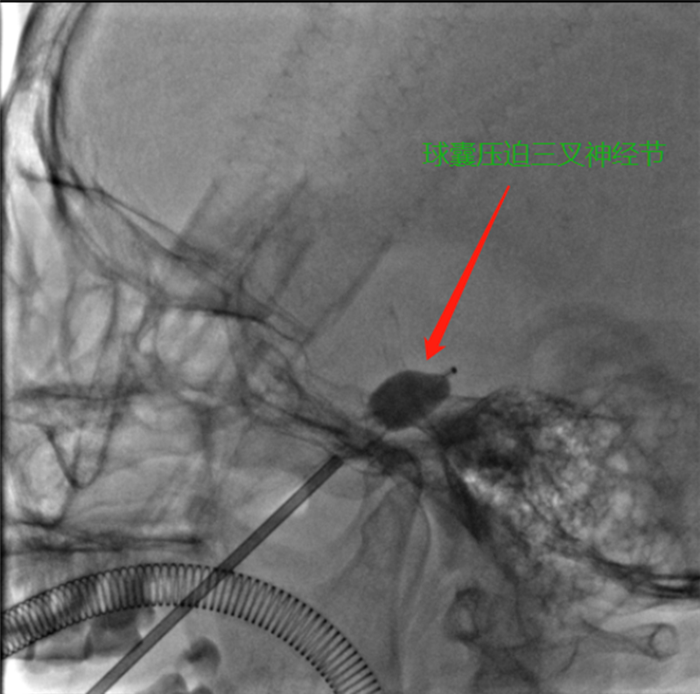

高婆婆入院后,川北医学院附属医院神经外科主任组织全科进行讨论,考虑患者高龄,开颅行微血管减压术风险高,结合患者及家属想进行微创治疗的意愿,决定为患者行经皮穿刺右侧三叉神经节球囊压迫术,解除患者疼痛。

3月26日,在该院各科室的通力配合下,进行了球囊手术。手术利用穿刺针在患者右侧面部,一针即中靶点,仅用10余分钟,即成功完成。术后患者疼痛消失,感觉面部轻松,脸上露出了久违的笑容。术后第三天高婆婆就康复出院,并赠送锦旗对该院治病效果表示满意。

川北医学院附属医院引进治疗三叉神经痛的新技术,经皮穿刺三叉神经节球囊压迫术,此技术具有微创、安全、费用低、无痛苦、住院时间短、疗效显著等优点。手术时间10到20分钟,患者住院2至3天即可出院,治疗后可快速康复。该手术属功能神经外科范畴,为该院神经外科首例,填补了科室在此领域的空白,为三叉神经痛患者提供了一种新的微创治疗方法。